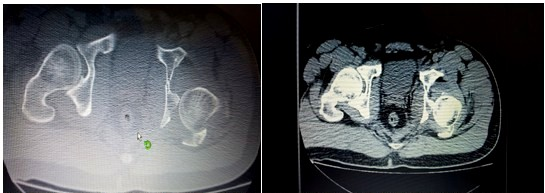

Dicho paciente fue atendido en el momento de su recepción en el área de código rojo, se valoró y se siguió el protocolo vigente para la atención de los pacientes politraumatizados implementado en nuestro centro. Se realizaron radiografías de las zonas afectadas, incluida una tomografía de la pelvis ósea. (Figuras 1 y 2).

Tras su control en dicha área se diagnosticó una fractura intraarticular del tercio distal del radio derecho y una fractura luxación posterior de cadera derecha.